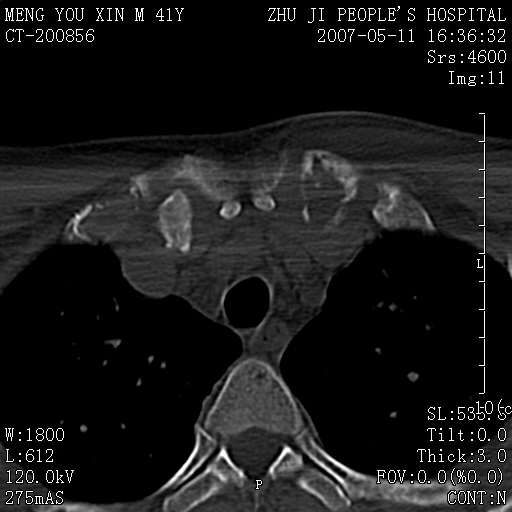

标题: CT8190:左锁骨胸骨端骨病,请会诊.

一周前左肩部酸痛,三天前颈部扭伤,后颈部摄片示颈椎病.现胸锁关节处肿痛明显.无发热.自诉三年前车祸安全气囊弹出.

左侧锁骨近端膨大,骨皮质中断,并见少许骨膜反应,内见破坏,边缘见筛孔征,无硬化.因此考虑骨巨细胞瘤可能.

1,不支持结核,此例胸壁肿胀不明显,锁骨后方是局限性肿物而非脓肿,考虑为恶性肿瘤2,左侧锁骨近端膨大,骨皮质中断,并见少许骨膜反应,内见破坏,边缘见筛孔征,无硬化.因此考虑骨巨细胞瘤可能.